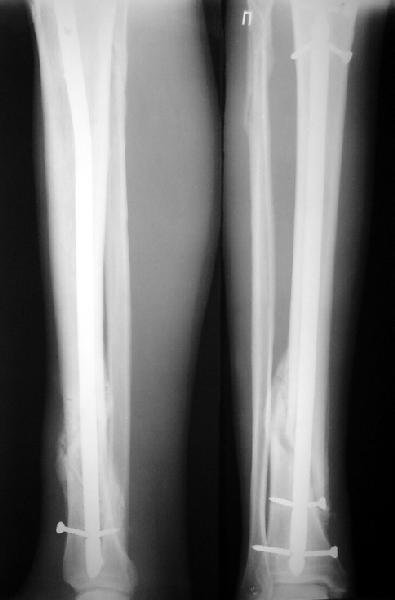

На мой взгляд, на снимках, приведённых Вами - неправильно сростающийся перелом дистальной трети большеберцовой кости, состояние после остеосинтеза интрамедуллярным гвоздём.

Как Вы пишите снимок под номером 1 - менсяц после операции, под номером 2- два месяца после операции.

Вы не послали послеоперационный снимок, поэтому трудно судить о состоянии редукции после операции.

I think that the X-Rays show S/P IMN of Spiral # of the Distal Tibia consoles in misalignment.

You wrote that a picture number 1 - f month after the surgery, and number 2-two months after the surgery.

You have not sent a postoperative X-Rays; so it's impossible to discuss about the condition of a reduction after operation.